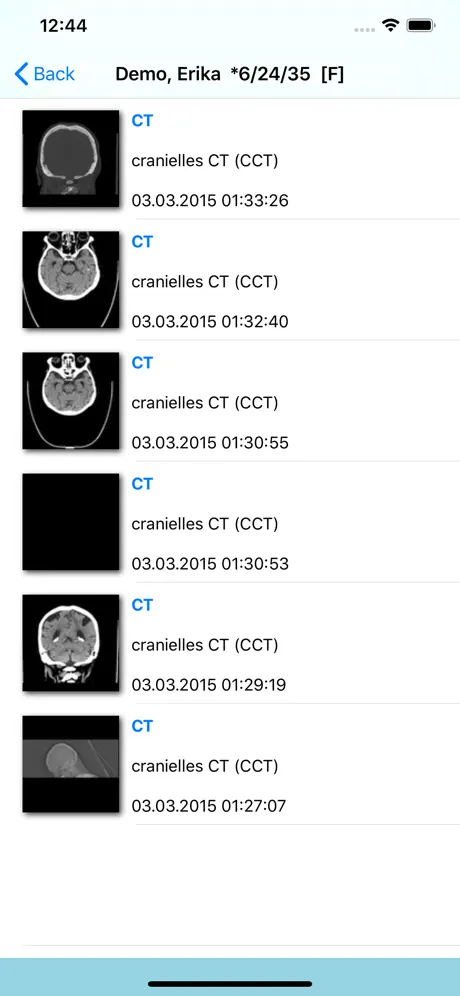

- Thumbnailvorschau

- Anzeige von DICOM Objekten

- Thumbnailvorschau

- Anzeige von DICOM Objekten